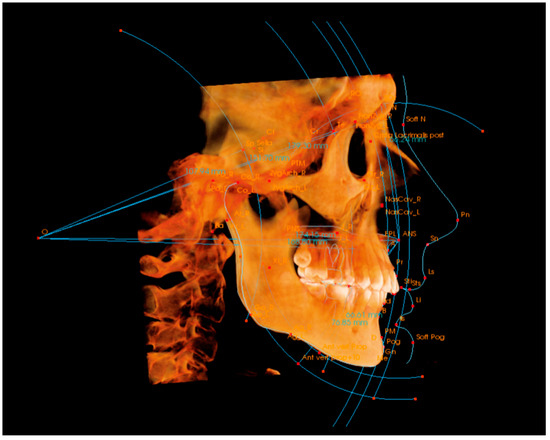

3D 스캔 분석

Primescan / TRIOS를 통한 정밀 치열·교합 데이터 수집

정확한 치아 배열과 교합 상태를 3차원으로 분석합니다